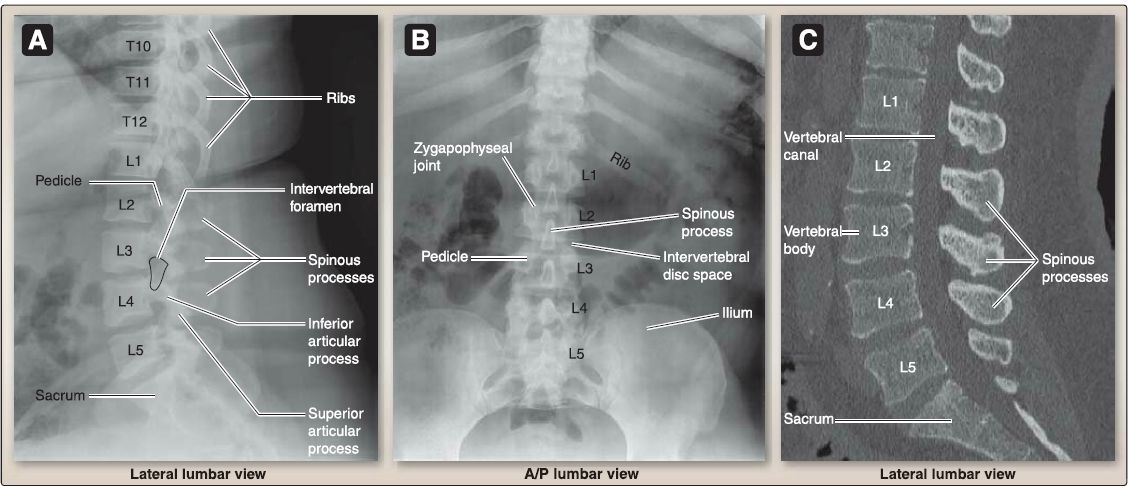

3. Lumbar (L 1-L5): As shown in Figures 7 and 8, lumbar vertebrae have large, kidney-shaped bodies and large, triangular vertebral foramina. Their articular facets are oriented in the sagittal plane, and they have short, hatched-shaped spinous processes. A mammillary process is located on the superior articular process.

Figure 7:Lumbar regional features.

Figure 8 :Plain film, A/8 and computed tomography (CT), C.